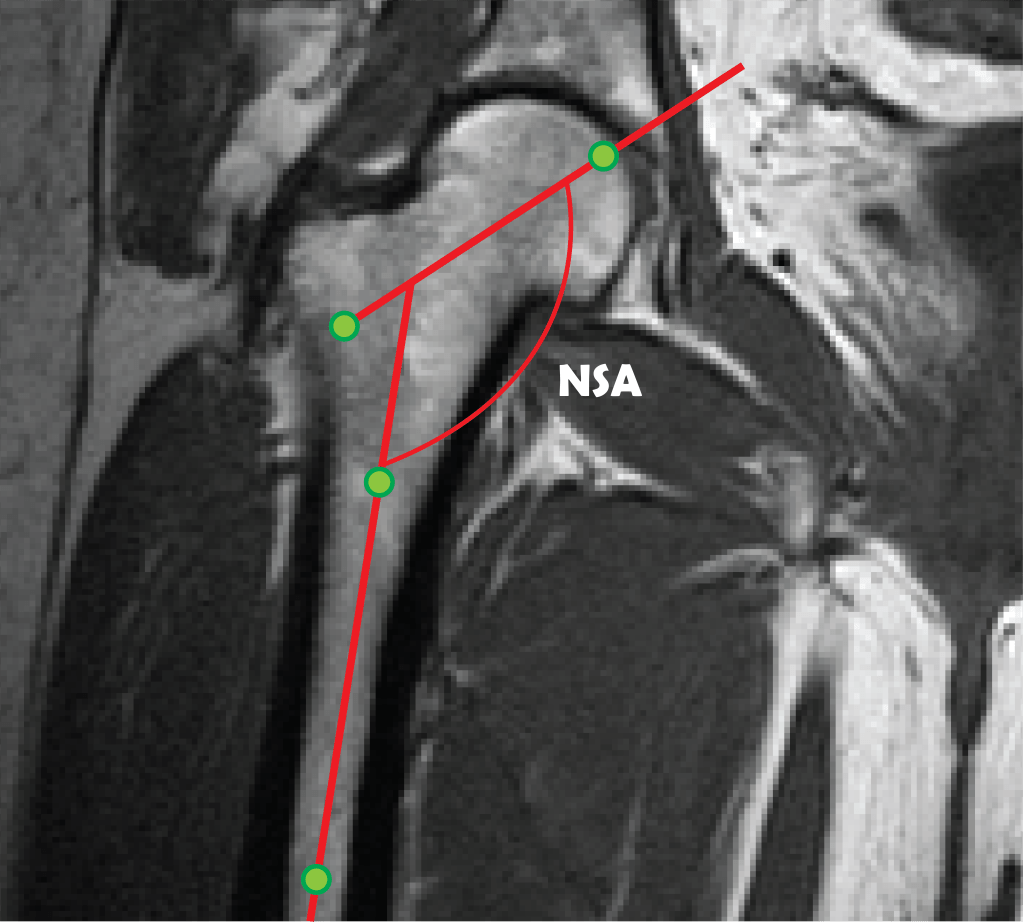

Morphological analysis of pelvic images

Musculoskeletal disorders accounts for most of the idiopathic pain cases worldwide. Diagnosis of musculoskeletal disorders is hampered due to the fact that early disorder stages often progress asymptomatically with up to 25% of mid-age adults having femoroacetabular abnormalities without experiencing any discomfort. This project combines machine learning with shape analysis for early diagnosis and quantification of spinal and pelvic abnormalities.